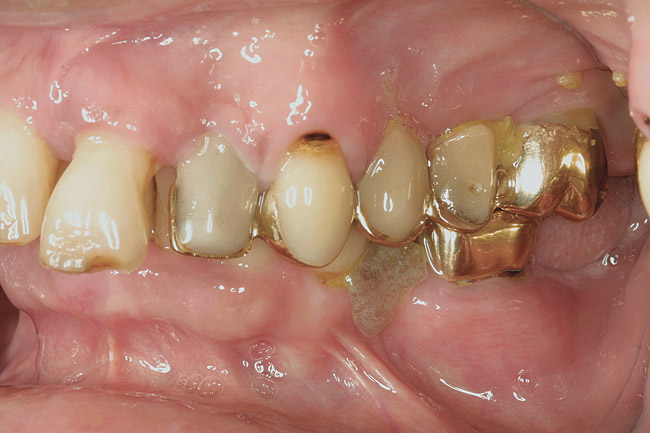

Most practitioners are currently taught to diagnose a D3 root-surface lesion (Figure 4) as active caries. The root surface is soft, sticky, cavitated, and may have debris that is easily removed with gentle palpation with the side of the explorer. Color changes may range from yellow orange/light brown to dark brown/black. The recommended treatment for D3 root-surface lesions includes remineralization of the root surface with products (pastes and varnishes) containing fluoride, calcium, and phosphate and subsequent restoration of the lost root-surface structure.

It is the experience of the authors that remineralization therapy applied to D3 root surfaces has the potential to result in root surfaces that, although discolored and cavitated, are completely hardened to a glassy, shiny surface. This allows the practitioner to preserve tooth structure that would otherwise be removed during preparation and provide a minimally invasive restoration. In cases where there is minimal cavitation in non-esthetic areas, the practitioner may opt to monitor the root surface for further change instead of placing a restoration. This classification system will aid the practitioner in diagnosing and monitoring these root surfaces.

Figure 4  This root surface is black and cavitated. When exploring with the side of the explorer, this root surface will feel soft and sticky, and it may be possible to remove soft debris from this lesion.

Figure 4